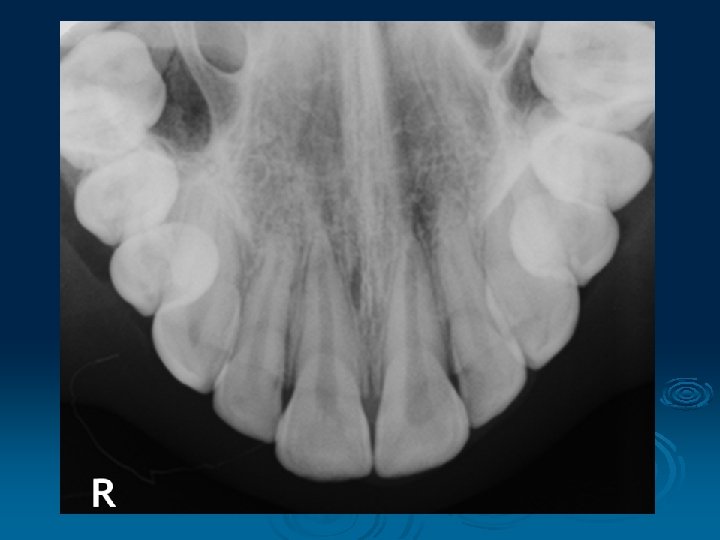

4. Occlusal Radiograph § A highly detailed x-ray taken with the x-ray plate placed between your teeth § It is useful to look closely at the front teeth (top or bottom) to check for any extra teeth or pathology § A special type of occlusal radiography technique can help demonstrate stones in the salivary glands in the floor of the mouth